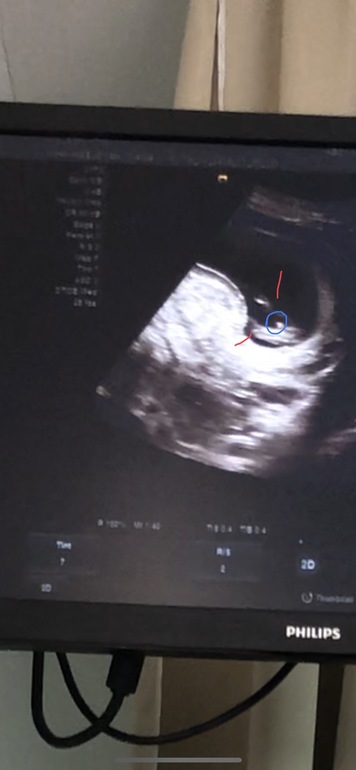

Добрый день))) на скринингн сказала ,что 90% мальчик ))) очень ждём и верим ))

Зелёным ножки обозначила ,в кружочек наши 90% надеюсь это сыночек 🙏🏻

Добрый день ,была на скринингн ,сказали 90% мальчик )) но пока это не 100,потому что срок не такой уж и большой )) вот фото )) надеюсь это наш сыночек🙏🏻 Через неделю схожу уже точно отпишусь )

Красным это ножки )))